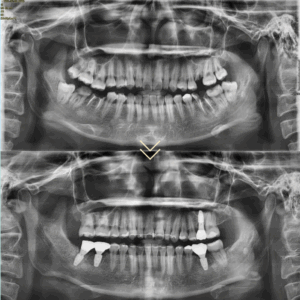

교정을 먼저 진행하면서

왼쪽아래의 뿌리만 남아있던 어금니를

가장 먼저 발치해주었습니다.

이후 오른쪽 위 사랑니와

심하게 손상되어 뿌리만 남아있던

왼쪽 위,오른쪽 아래 어금니를 발치해주었습니다.

이후 나머지 매복된 사랑니를 모두 발치하였고

교정을 통해서 쓰러져있던 치아들이

바로 세워졌습니다.

교정을 진행하여 치아들을 바르게 세운 뒤

발치를 진행했던 공간들을 적절하게 확보하여

임플란트를 식립하였습니다.

임플란트 보철까지 완성한 모습입니다.